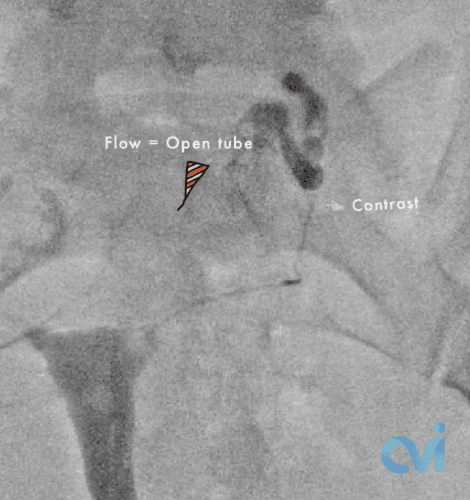

During the procedure, similar to a pelvic exam at your OBGYN, you lay on your back and a speculum is placed into the vagina. Then a small catheter is inserted through the cervix and a contrast agent, or dye, is injected into the uterus so an X-ray image of the uterine cavity can be obtained. When a fallopian tube blockage is identified, another smaller catheter and wire are threaded into the fallopian tube to open the blockage.

Selective salpingography and fallopian tube recanalization is a safe and effective treatment. Success rates are high in experienced hands with dedicated equipment in the appropriate setting.